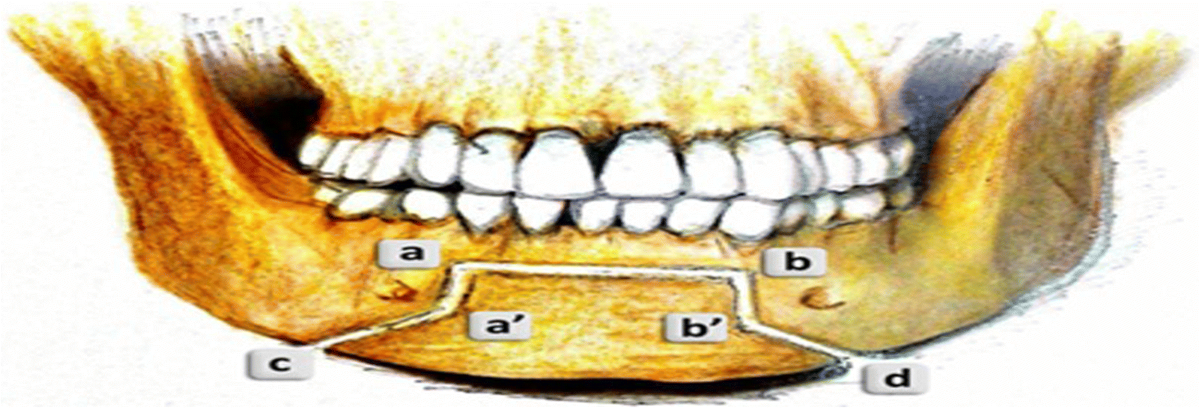

16mm genio-only projection with jawline implants. Clearly a trimax case, but for some bizarre reason, Ramieri chose to only do a genio instead. Note the deep mentolabial fold and the bunching around the submental from the transition between the chin and the rest of the mandible.

Look at the transition between the chin and the mandible; clearly a step-off. Is this because of chin shaving/reduction having the opposite of a tightening effect, or just simply poor technique on Ramieri's part?

Genio is supposed to be a relatively simple surgery, and hard to mess up. Is it really just poorly planned cuts or something else about the technique? Or is the step-off exaggerated in these after photos because of soft tissue swelling? Is the problem case-specific, or is Ramieri generally bad at genioplasties? I don't think it's fair to judge based on 2 cases and a few supposed forum anecdotes, but it doesn't set a good precedent for sure.